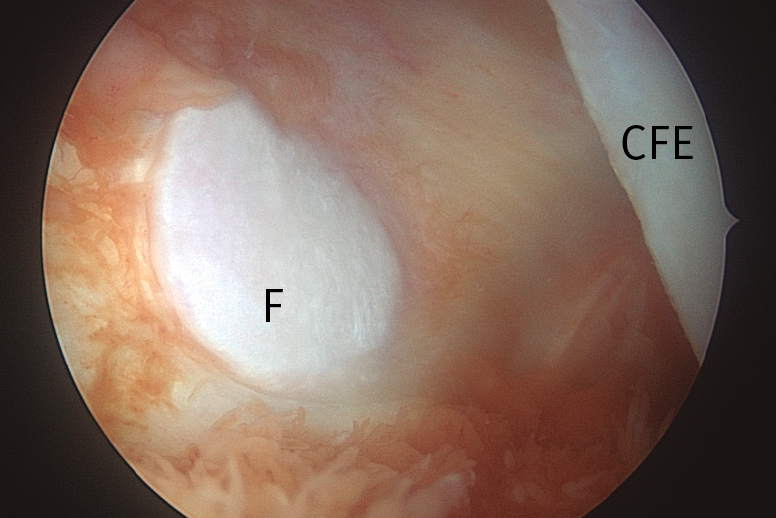

Esta técnica no forma parte de los gestos habituales durante una artroscopia rutinaria de rodilla, pero resulta muy útil en cirugías como la resección de ciertos tumores (destacando por su frecuencia la sinovitis villonodular pigmentada) (Figura 7), el abordaje a la fabela (Figura 8), la extracción de cuerpos libres o el reanclaje de avulsiones óseas de la inserción tibial del LCP. Además, la creación de este portal permite una buena visualización de la porción posterosuperior de ambos cóndilos femorales y de la cara posterior del LCP, del ligamento de Wrisberg, del tendón poplíteo y de la unión meniscocapsular de ambos meniscos(24)(Figuras 9 y 10).

Figura 8. Visión transescotadura, compartimento posterolateral, rodilla izquierda. Imagen de la carilla articular de la fabela, hueso sesamoideo articular incluido en el tendón del gastrocnemio externo. CFE: cóndilo femoral externo; F: fabela.